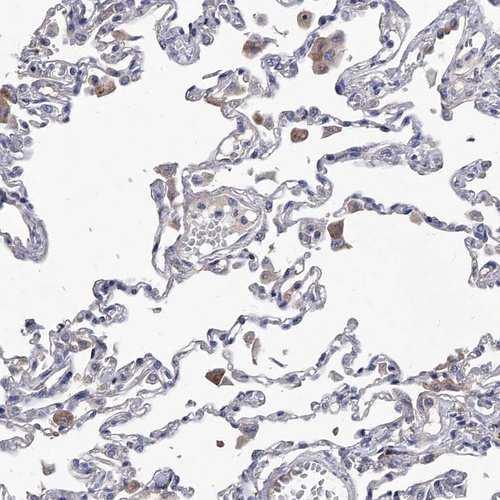

Immunohistochemical staining of human lung shows moderate cytoplasmic positivity in macrophages.